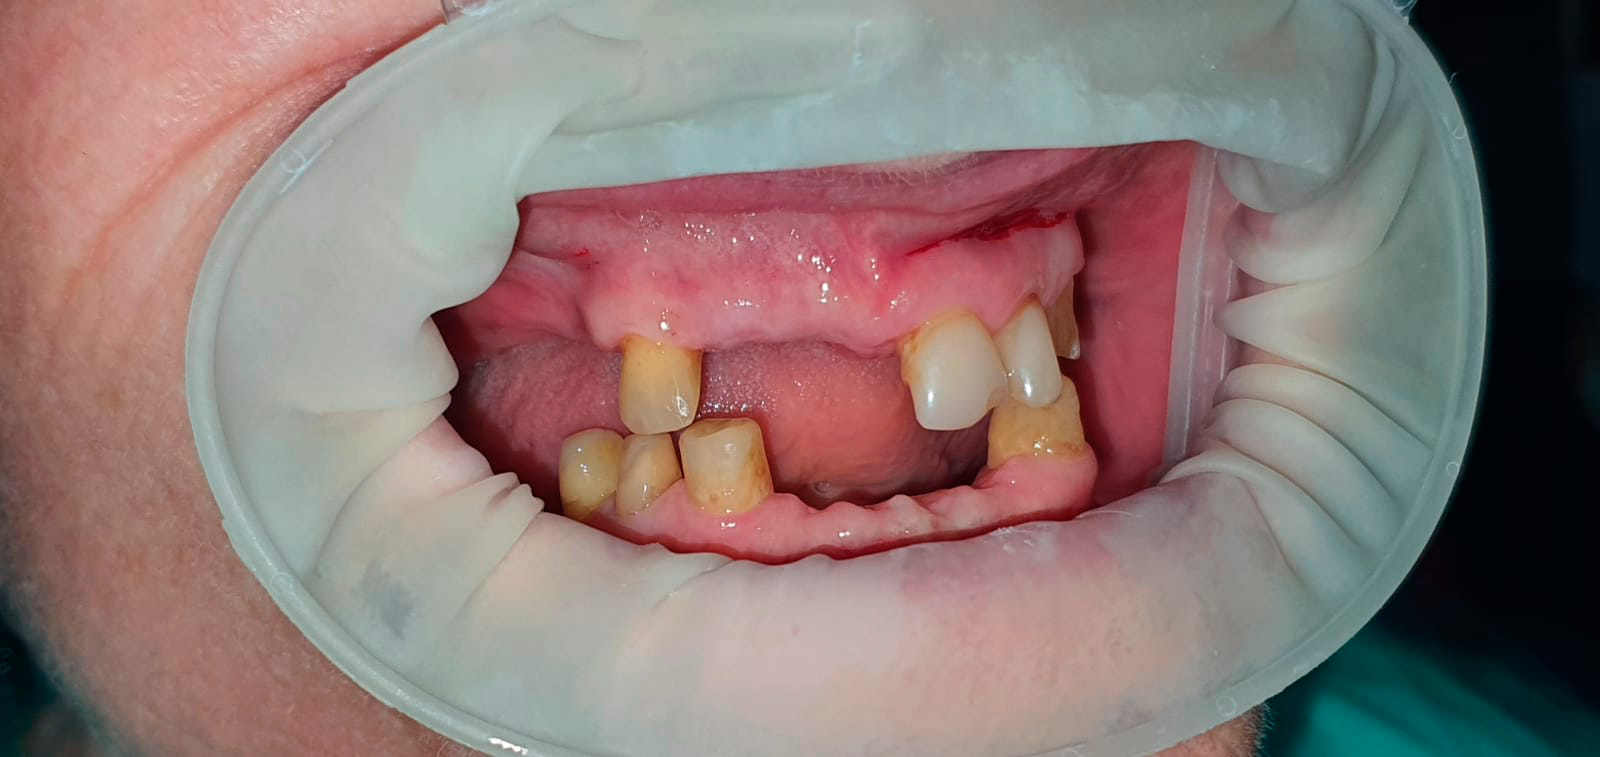

Временные композитные реставрации. Промежуточный этап в ортопедическом лечении. Выполнил врач Краснов Д.А.

До

После